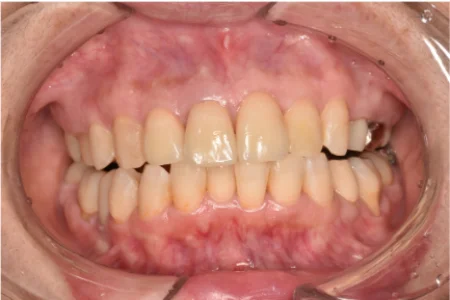

治療後

| 行ったご提案・治療内容 | 新たに被せ物を作り変える際に、再度、保険治療内の素材で作製することも可能でしたが、時間が経つと今回のようにレジンが剥がれてくるリスクや、色味をこれ以上綺麗にするのは難しいことをお伝えしました。 また、神経を抜いている歯はホワイトニングで白くすることは難しいため、審美性を求めるのであれば右上側切歯(2番)も被せ物で治療することをご提案しました。 患者様に新たな被せ物の素材をヒアリングしたところ、「天然歯に近い自然な白さの色味がいい」とご希望でした。そのため、患者様のご希望の色味にするには自費治療の素材「ジルコニア」が適していることや、費用面(保険治療は1歯約1万円、ジルコニアは1歯約10万円)も丁寧にご説明したところ、ご了承を得ましたので治療を進めました。 被せ物を外したところ、虫歯が1本見つかりましたので、虫歯を取り切ってから被せ物の型取りを行いました。 |

| 術後の経過・現在の様子 | 治療後から現在まで、腫れや痛みはなく、噛み合わせなど使用感も問題ありません。 色味も周囲の歯と違和感がない、自然な白さに仕上がり、患者様にご満足いただけています。 |